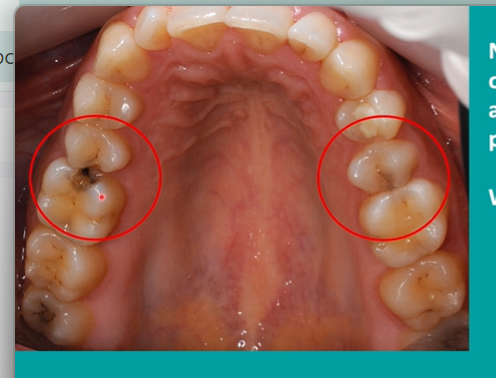

spot the caries

lower right and left second molars

are they the same colour? - the lower right has a fissure sealant

black one indicates staining and possible caries

compare the distal aspect of the upper 5s and the mesial aspects of the upper 6s - what can you see?

in the black - areas within the lesion there are still areas of remineralisation

patient chipped tooth - cannot brush correctly - caries process